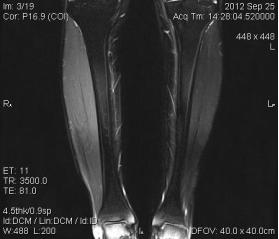

典型病例:患者,男,40岁,体能训练致左小腿肌肉撕裂伤并巨大血肿,给予脉冲磁疗、中频电疗和下肢肌肉训练指导后,血肿逐渐消退,两个月后肌肉恢复正常,继续参加训练。